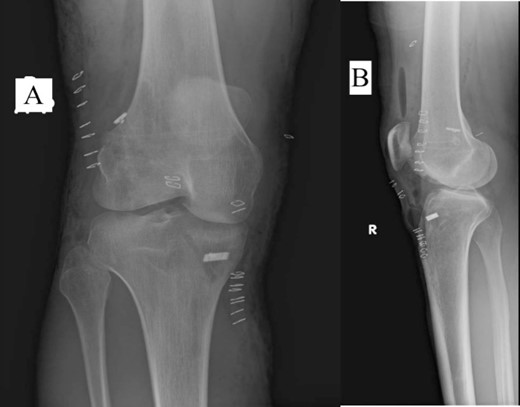

A 23-year-old male veterinarian presented to our out-patient department postright ACL reconstruction with hamstring autograft, PHMM tear by all-inside repair via sMCL pie-crusting technique, and lateral extra-articular tenodesis (modified Lemaire) in June 2023. A preoperative plain radiograph of the right knee revealed no evidence of HO (Fig. 1). No evidence of heterotopic ossification was detected in the right knee on plain radiographs taken 2 weeks postsurgery. (Fig. 2). Five months postsurgery, plain radiographs revealed new bone formation at the medial femoral condyle, precisely where the sMCL femoral origin was located (Fig. 3). The patient was asymptomatic and continued with rehabilitation. Seven months after the surgery, the patient started to complain of pain and clicking sensations when the right knee was flexed beyond an angle of 130°. Magnetic resonance imaging revealed consolidation of the newly formed bone, leading to a diagnosis of HO post-sMCL pie-crusting (Fig. 4). Nine months following surgery, the patient began to feel a bony mass on the medial side of the right knee. A plain radiograph and computed tomography (CT) scan revealed the complete formation of a bone island (Fig. 5). The past surgical history of this patient revealed that he had undergone left knee ACL reconstruction with hamstring autograft in December 2021, which failed and was complicated by a PHMM tear. The patient had presented to our facility for a revision. A revision ACL reconstruction was done using a bone-tendon-bone (BTB) autograft and PHMM tear all-inside repair via the sMCL pie-crusting technique in February 2022. A 2-year follow-up of the left knee, including physical examination and 3D-CT scans (Fig. 6), revealed no symptoms or signs of HO, although the same technique of sMCL pie-crusting was employed. Our patient suffered no head trauma during treatment. Past medical, drug, allergy, family, social histories, and reviews of systems were irrelevant to our case.

Plain radiograph of right knee AP (A) and lateral (B) 2 weeks postoperative showing no HO.